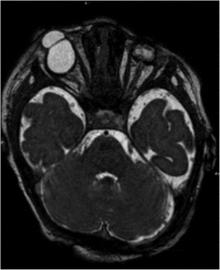

MRI revealed microphthalmos in the left ocular globe and a coloboma-like structure in the right in a female infant with Fraser syndrome.

Bilateral cryptophthalmos with microphthalmos in the left ocular globe and abnormal right ocular globe in a female infant with Fraser syndrome.